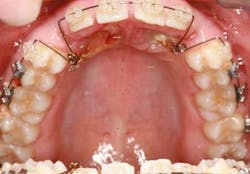

When a full permanent dentition is present (with the exception of impacted canines), the labial/palatal position of the canine will have an influence on what the provider can do. (1) Arguably, obtaining a CBCT is considered mandatory and will allow for a more inclusive treatment plan creation. If angulation is favorable, then consideration to remove the primary canine and wait six months to see if there is movement of the permanent canine is an option. If extraction of the canine(s) is needed, then a premolar substitution, which is dependent on occlusion, can be used in the space. An implant can also be an appropriate alternative. When pulling a canine into the occlusal arch, there is risk involved. Trauma to adjacent teeth (root resorption) and ankylosis are some of the most common complications.The patient was put in full orthodontics and referred to a surgeon for extraction of the primary canines, exposure, and placement of retention on the impacted canines to pull them directly down from their current position.

A ballista appliance was used to prevent a facial pull of the canines in order to avoid and prevent resorption of the roots of the lateral incisors. As movement progressed over the course of the next year, eruption of the canines was considered a success. Once in position, they will be pulled facially into occlusion.